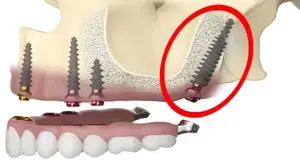

Zygomatic Implants

Alternative implants anchored in the cheekbone for severe bone loss.

Pterygoid Implants

Placed in the pterygoid bone for posterior tooth replacement.